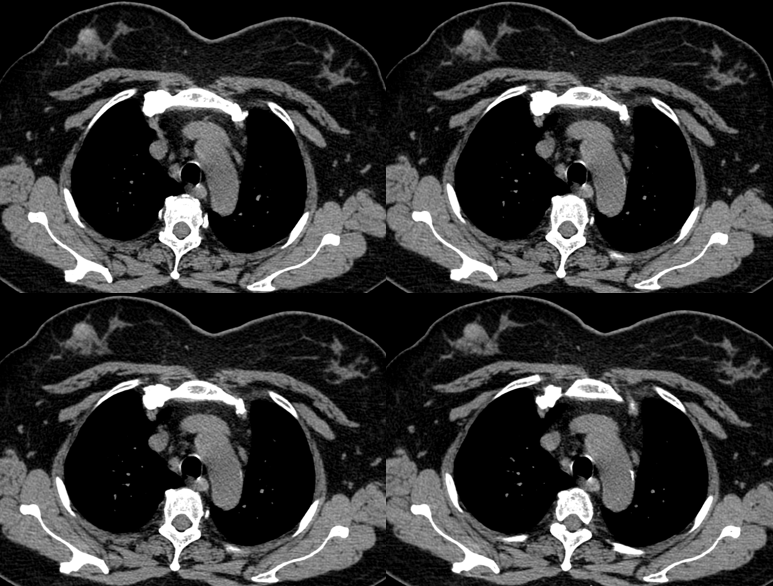

乳腺炎:包括急、慢性乳腺炎和乳腺脓肿,多见于产后哺乳期妇女,急性乳腺炎常有典型的临床症状-红、肿、热、痛;若治疗不及时可形成慢性乳腺炎或乳腺脓肿。MG 表现片状致密影,边缘模糊,患处皮肤水肿增厚,皮下脂肪层模糊;MRI-T1WI 表现为片状低信号,T2WI 高信号,信号强度不均匀,边缘模糊,皮肤水肿、增厚,增强 MRI 通常表现为轻至中度强化,且以延迟强化为主。